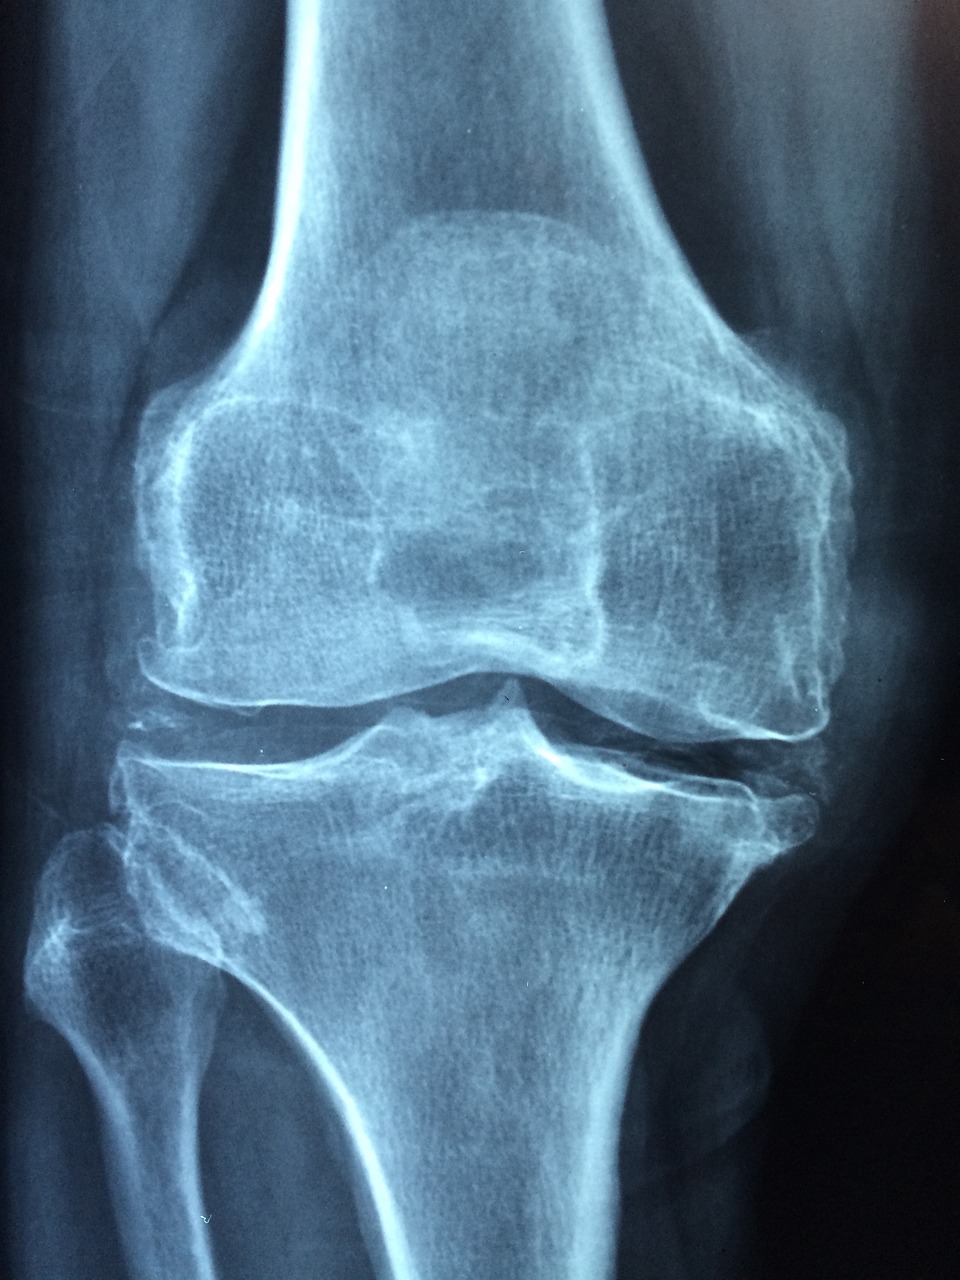

특히 연골이 닳기 시작한 50대 이상이나 퇴행성관절염 초기 증상이 있는 분들에게는 무릎에 체중이 실리는 동작은 오히려 부담이 될 수 있습니다.

무릎은 관절과 인대만으로 체중을 지탱하기엔 부담이 크기 때문에, 주변 근육이 받쳐줘야 합니다.

특히 허벅지 앞쪽의 대퇴사두근, 엉덩이 근육, 종아리 근육을 강화하면 무릎 부담이 줄어듭니다.